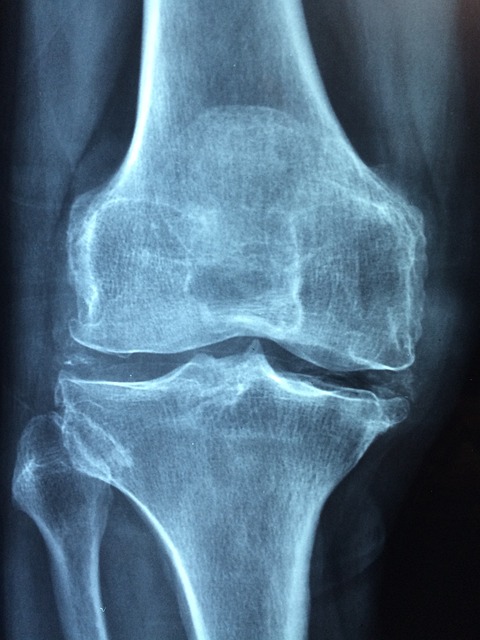

나이가 들수록 무릎 통증이나 관절이 뻣뻣한 느낌이 자주 느껴지시나요? 이는 퇴행성 관절염의 전형적인 증상일 수 있습니다. 하지만 적절한 걷기 운동은 관절염을 악화시키는 것이 아니라 오히려 예방과 관리에 큰 도움이 됩니다.